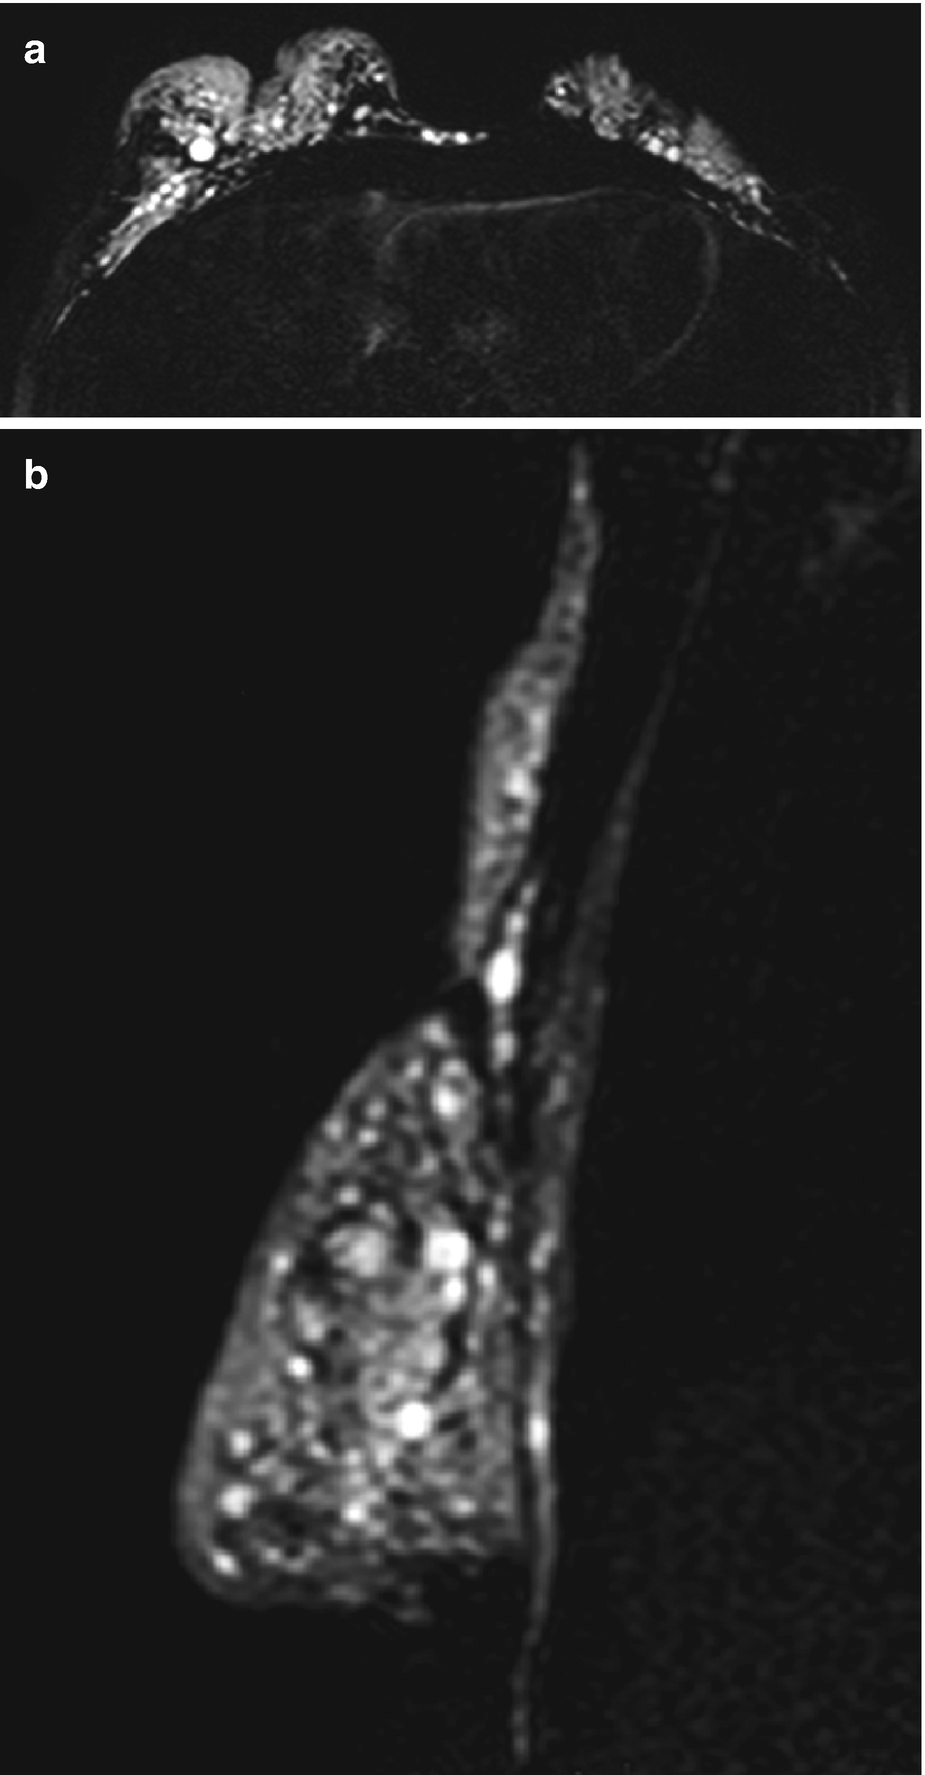

Magnetic resonance imaging (MRI) (a) T2-weighted axial sequence with suppression of fat and water (the so-called silicone-only sequence) reveals deformation and retraction of both breasts, accompanied by the presence of numerous hyperintense siliconomas within the parenchyma, intermammary groove, and chest wall. (b) T2-weighted sagittal sequence with suppression of fat and water (“silicone-only”) clearly demonstrating silicone infiltration of the parenchyma, axillary region, and thoracic wall

The breast coils have a geometric design that provides a high signal-to-noise ratio in an area that spans both breasts, with extension to the chest wall and the axillae. This is very useful in the evaluation of silicone migration to soft tissues in patients with implants or a history of liquid silicone injection. Other considerations in the design of breast coils include patient comfort and open access for MR-guided markers and biopsies. The study is carried out with the patient in a prone position, which minimizes the effects of respiratory movements [18].